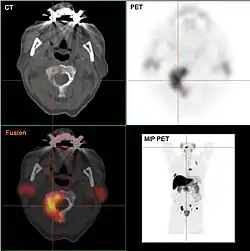

Außerdem etabliert sich immer mehr die Positronen-Emissions-Tomographie (PET) mit 18F-Cholin (radioaktiv markierter Tracer). Vor allem mittels 18F-Cholin-PET/CT kann zuverlässig Prostatakrebs-Gewebe von benigner Hyperplasie, chronischer Prostatitis und gesundem Prostatagewebe differenziert werden.[60][61]